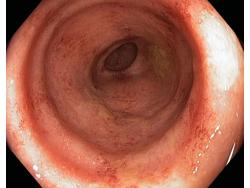

Zapalenie wrzodziejące jelita grubego